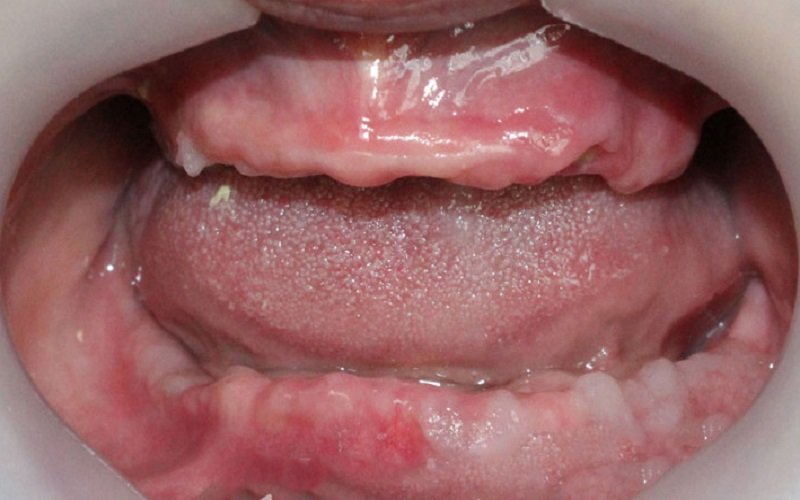

Đây là phương pháp phục hình lâu đời nhất và cũng là lựa chọn phổ biến nhất do chi phí tương đối thấp và kỹ thuật thực hiện đơn giản. Hàm tháo lắp gồm bộ răng giả được gắn trên nền nhựa hoặc khung kim loại, có thể dễ dàng tháo ra để vệ sinh hàng ngày.

Ưu điểm lớn nhất của phương pháp này là tính tiện lợi và khả năng phục hồi nhanh chóng chức năng ăn nhai cơ bản. Tuy nhiên, hàm tháo lắp cũng có những hạn chế như cảm giác không chắc chắn, dễ bị lỏng lẻo khi ăn nhai, gây khó chịu và đôi khi làm tổn thương nướu. Đồng thời, phương pháp này không ngăn ngừa được hiện tượng tiêu xương hàm, do lực nhai không được truyền trực tiếp xuống xương.

Bác sĩ thường chỉ định hàm tháo lắp cho những bệnh nhân có điều kiện kinh tế hạn chế hoặc không đủ sức khỏe để thực hiện các phương pháp cấy ghép Implant.